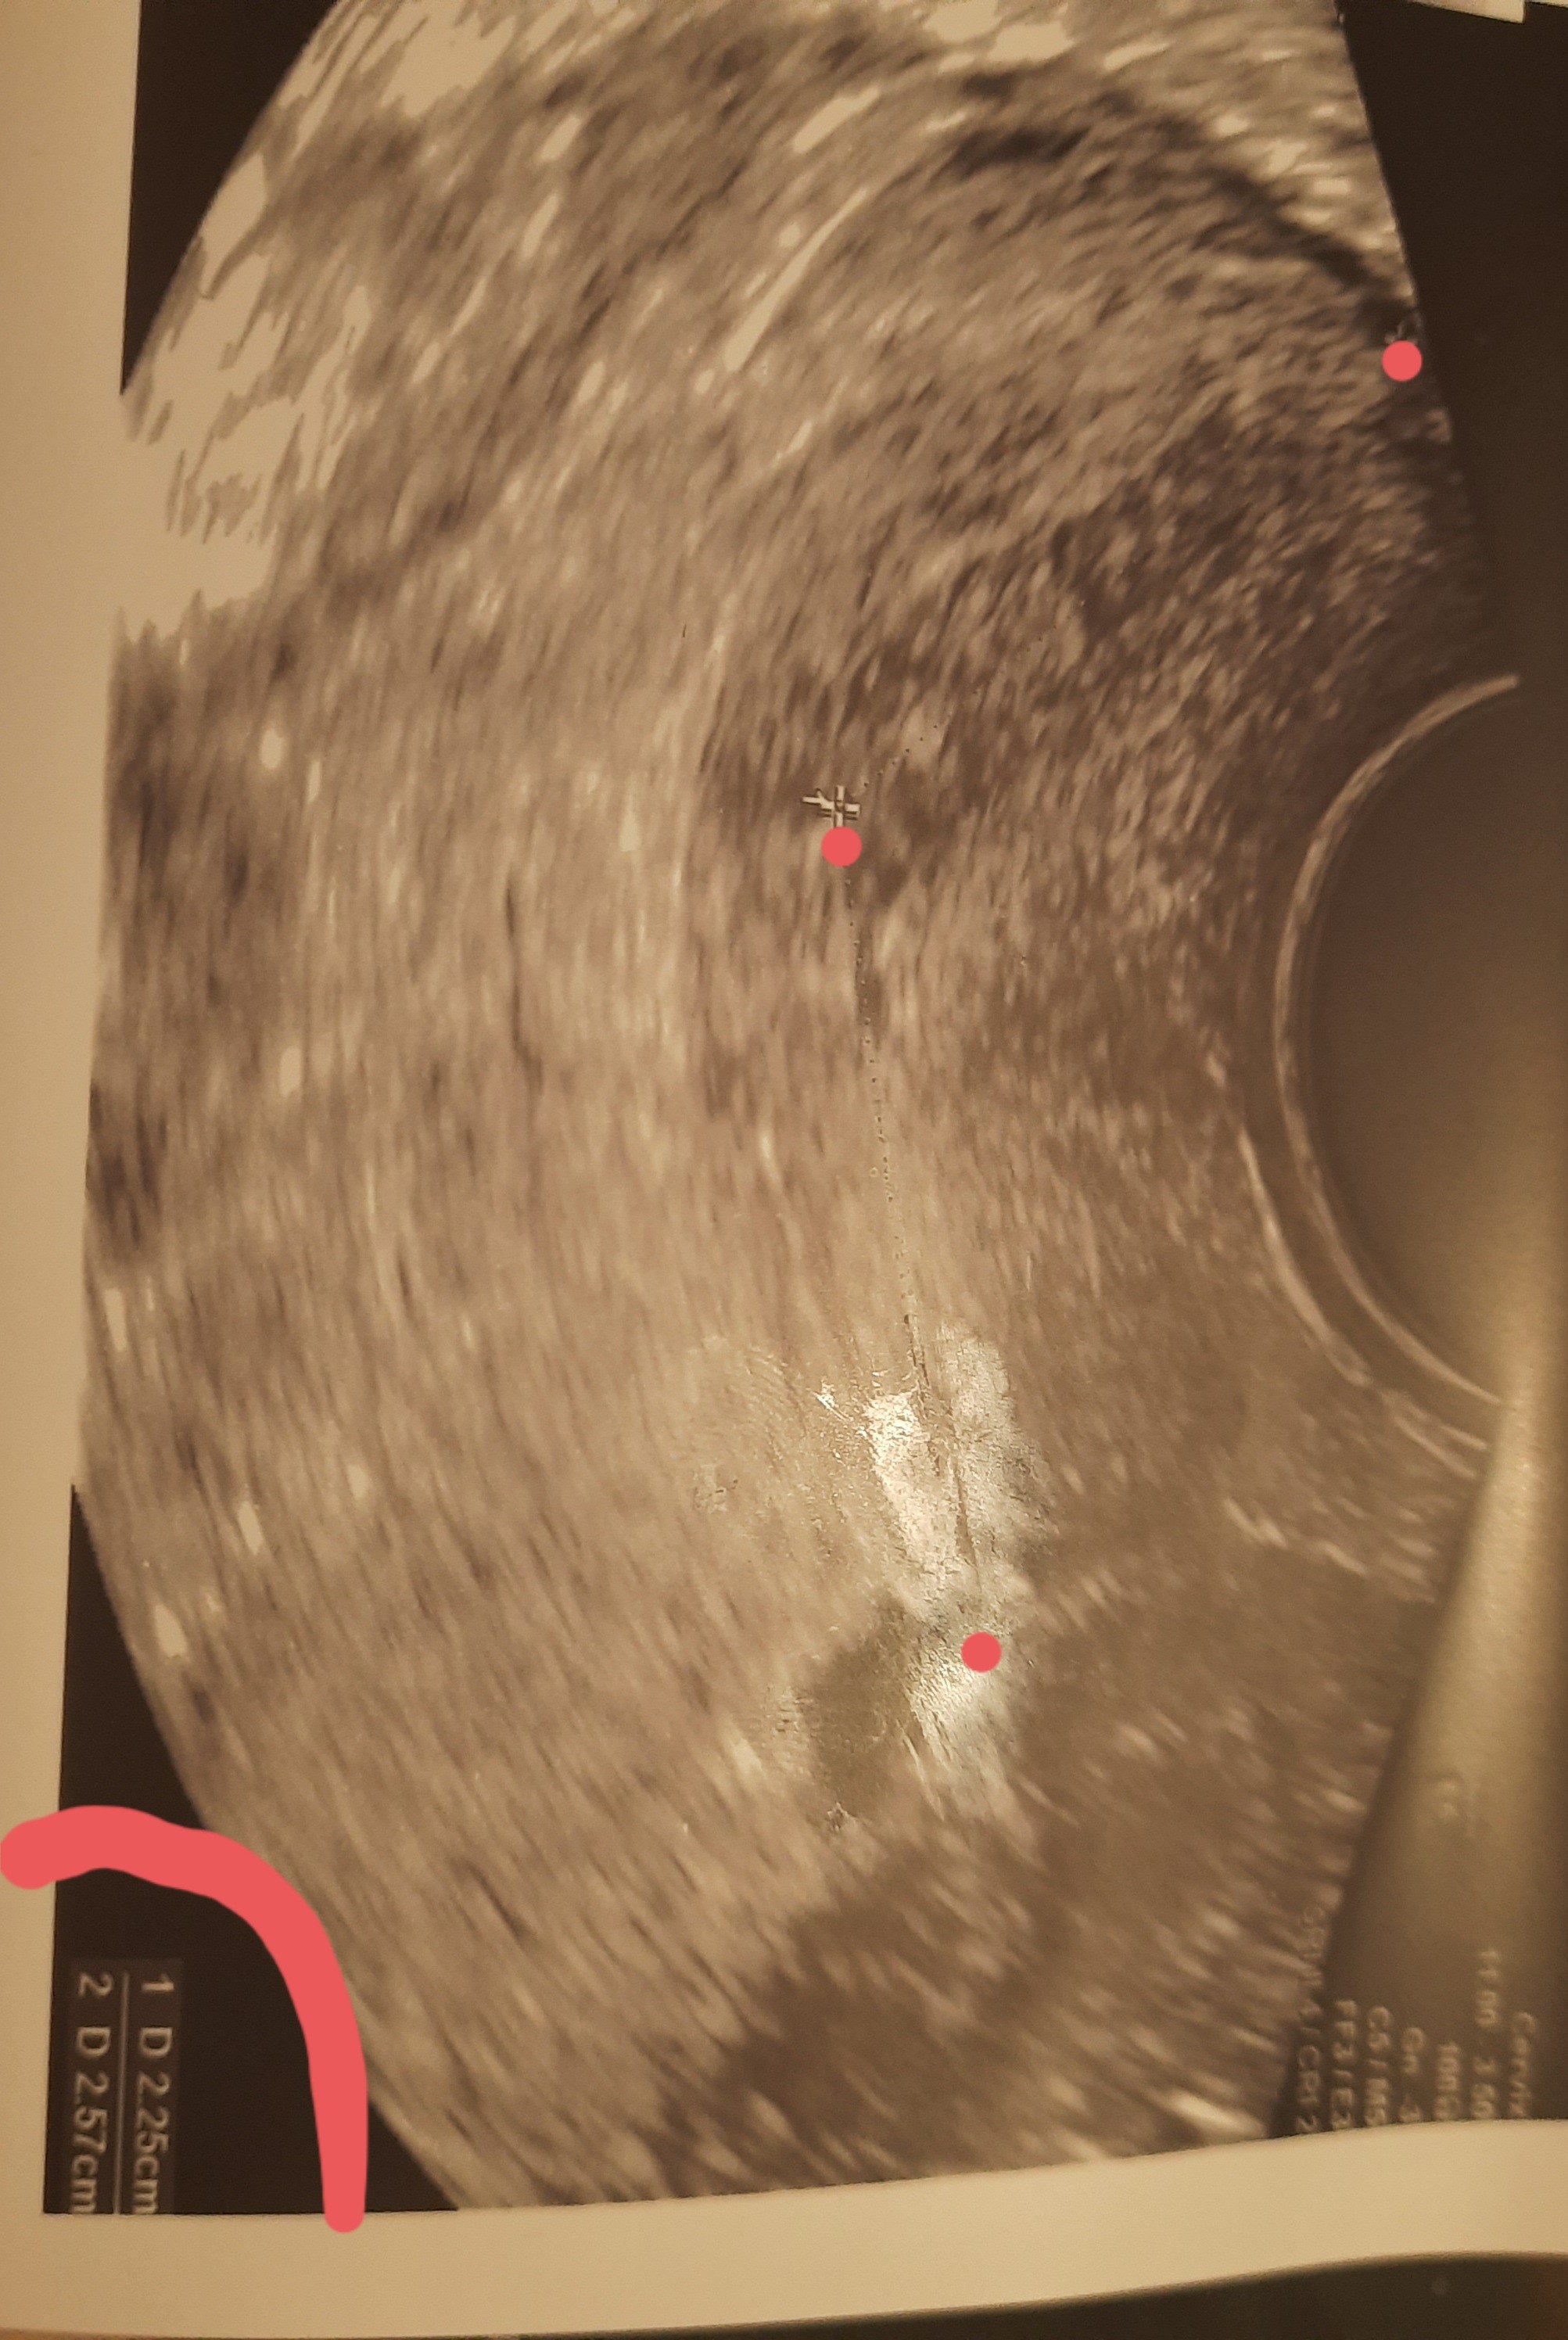

Czy ktoś mógłby wytłumaczyć mi jak to jest z mierzeniem szyjki? Te dwa pomiary się dodaje ? Jeden ginekokog twierdzi że tak a drugi ze nie i że skraca mi sie szyjka macicy bo ma tylko 2.25.

• 20220409_221344.jpg